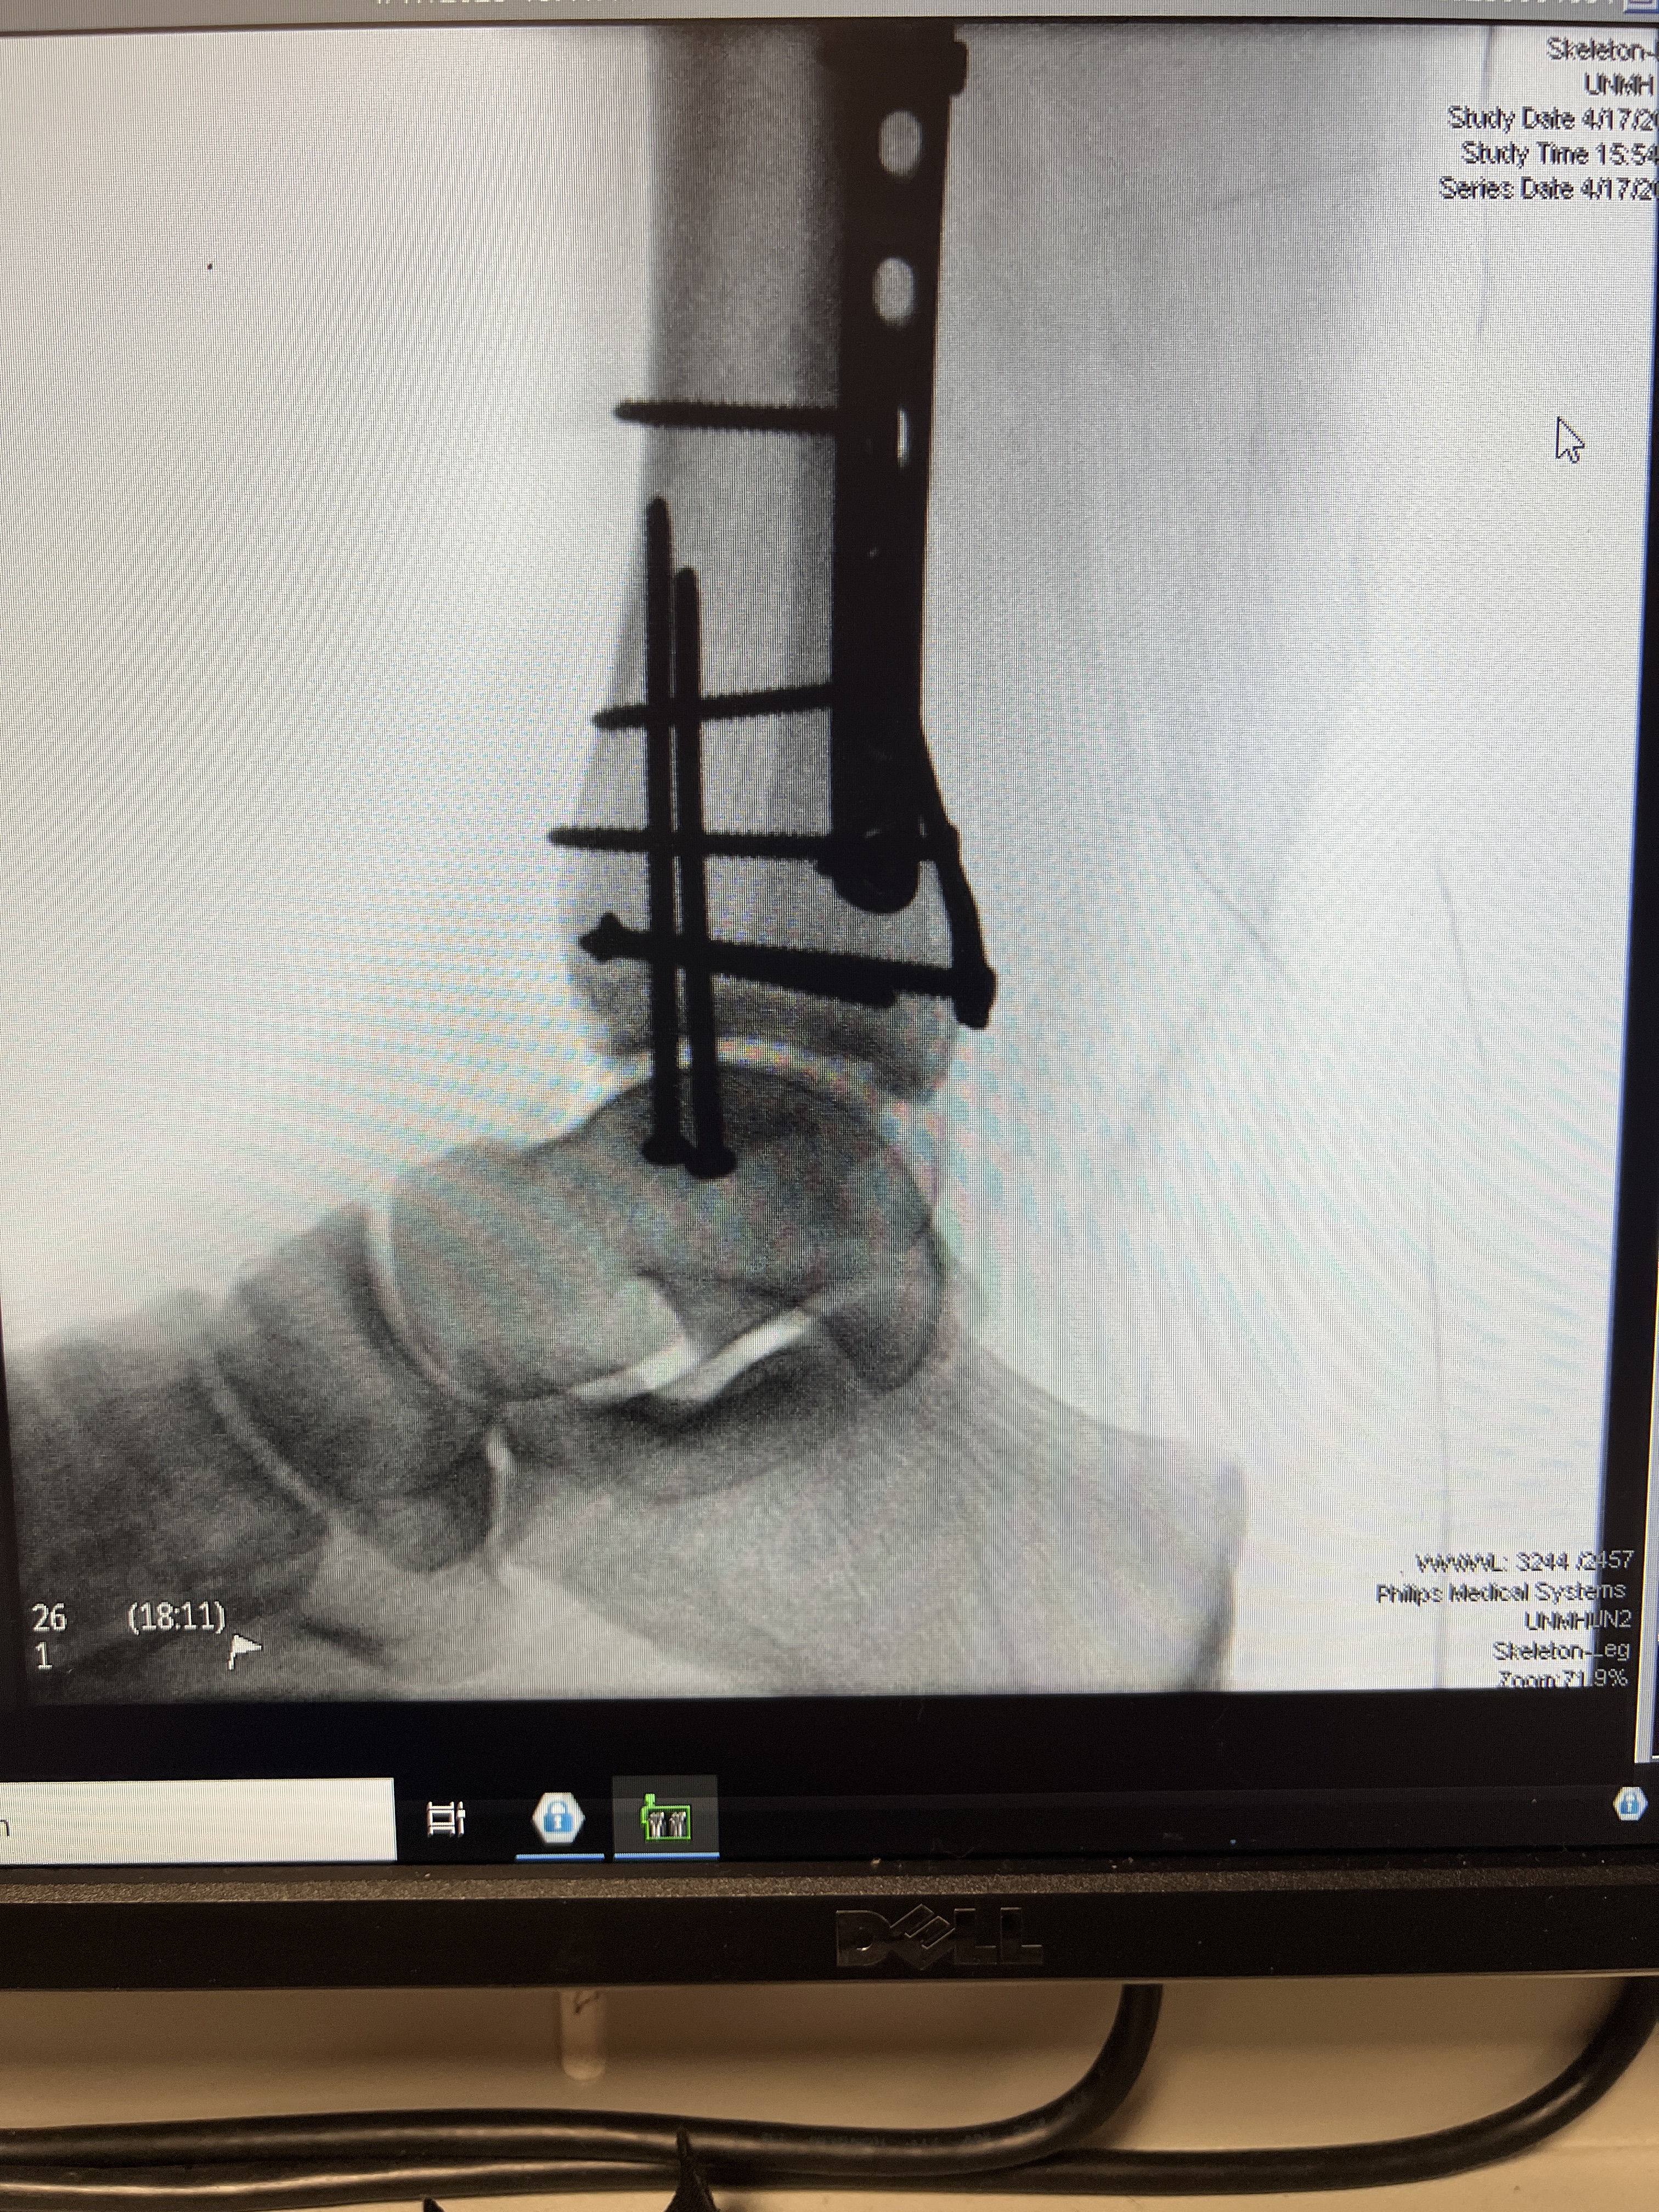

On Thursday afternoon April 17, 2025, I had my second and final successful ankle surgery at UNM Hospital. Dr. Wharton and his team installed all the internal hardware to support the healing of my three fractured bones. I did indeed feel like the Bionic Woman after I saw the x-rays days later. My husband managed through some hours of worry as my procedure started late and the orthopedic team did not update him promptly when I was out of surgery. He was grateful to join me when they wheeled me to my hospital room. We were both thankful to learn that the surgery went really well.

The next morning on Easter Sunday I was more than ready to go home. I had a visit by a sharp, informative and get-things-done orthopedic nurse who arranged for my hospital discharge and managed to take photos of my x-rays on the computer monitor so that I had those to show my local Henderson, NV orthopedic doctor when I had one. She explained when I should schedule an appointment, And…. I asked her the same question I had been asking nearly every nurse, doctor and medical technician I’d met. “Do you think that I’ll be able to go on my family’s trip to Europe in June?” She emphatically and confidently said, “Yes. You will!” She nodded her head and said that yes it would take some work and mobility devices, but I would absolutely be able to go. I was elated at her solid confidence. It reaffirmed mine!